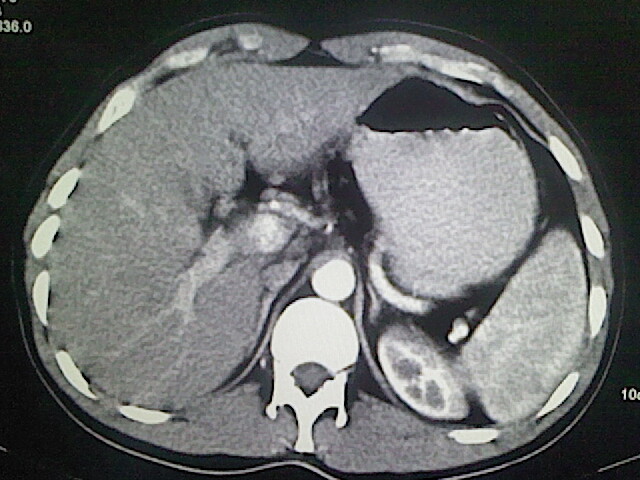

以下是引用卜一在2009-3-14 9:49:00的发言:[br]胆囊萎缩,胆囊壁不规则增厚,内部结构模糊,增强明显强化。另:肝左叶外侧段肝囊肿。支持:慢性胆囊炎!高度可疑:胆囊癌!

以下是引用余辉在2009-3-14 8:48:00的发言:[br]1)慢性胆囊炎。2)肝左叶外侧段肝囊肿。3)脂肪肝。[br]支持,胆囊萎缩,密度增高,不知b超具体有何提示,钙胆汁?结石?

以下是引用jiangjing在2009-3-14 10:18:00的发言:[br]1)慢性胆囊炎。2)肝左叶外侧段肝囊肿。3)脂肪肝。4.】建议行肝功能检查